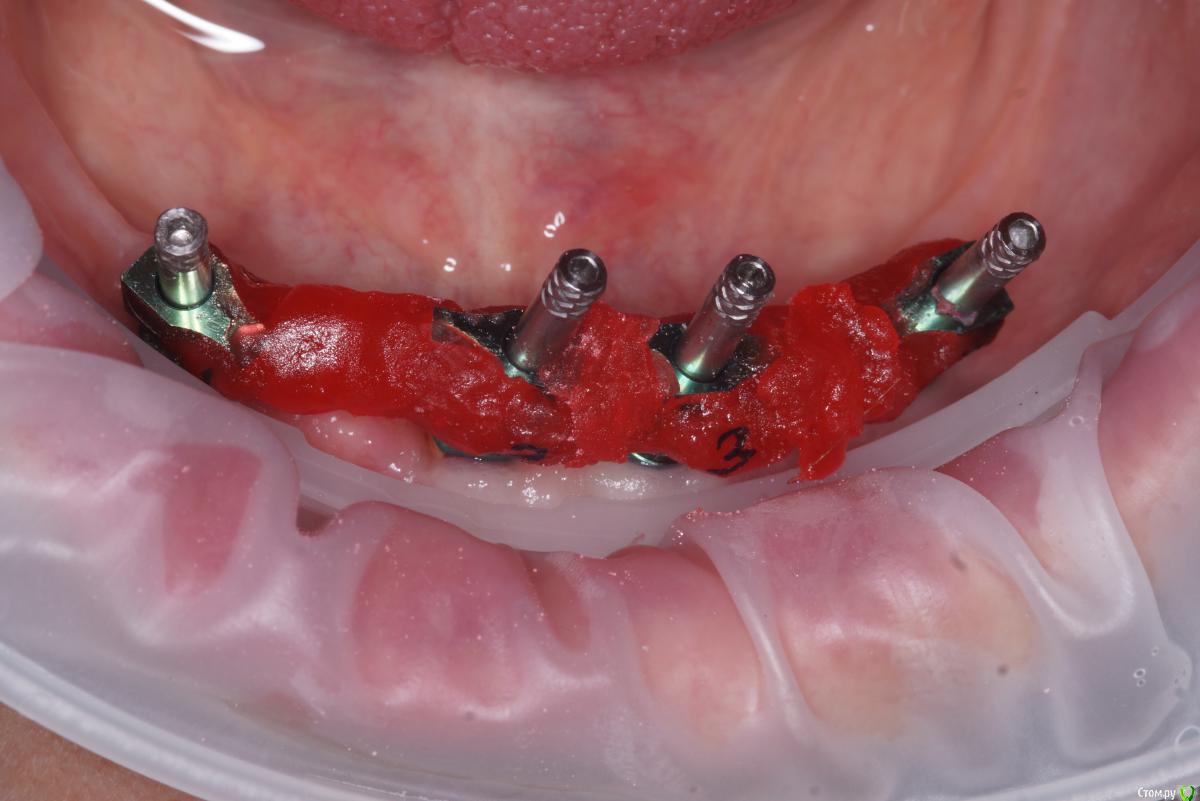

Пациент отходил 2 месяца, на осмотре при откручивании протеза периотест показывает на импланте 34 +50. Пятки вспотели. Отпиливаю от временного протеза часть, прикручиваю формирователь. Проверяю ии! -3. Блин, зря протез отпилил((

Ну, пора протезировать значит. Техник быстро готовит трансфер чек post-36568-0-78794200-1566455148_thumb.jpg

Прикручиваем балку post-36568-0-83457700-1566455323_thumb.jpg